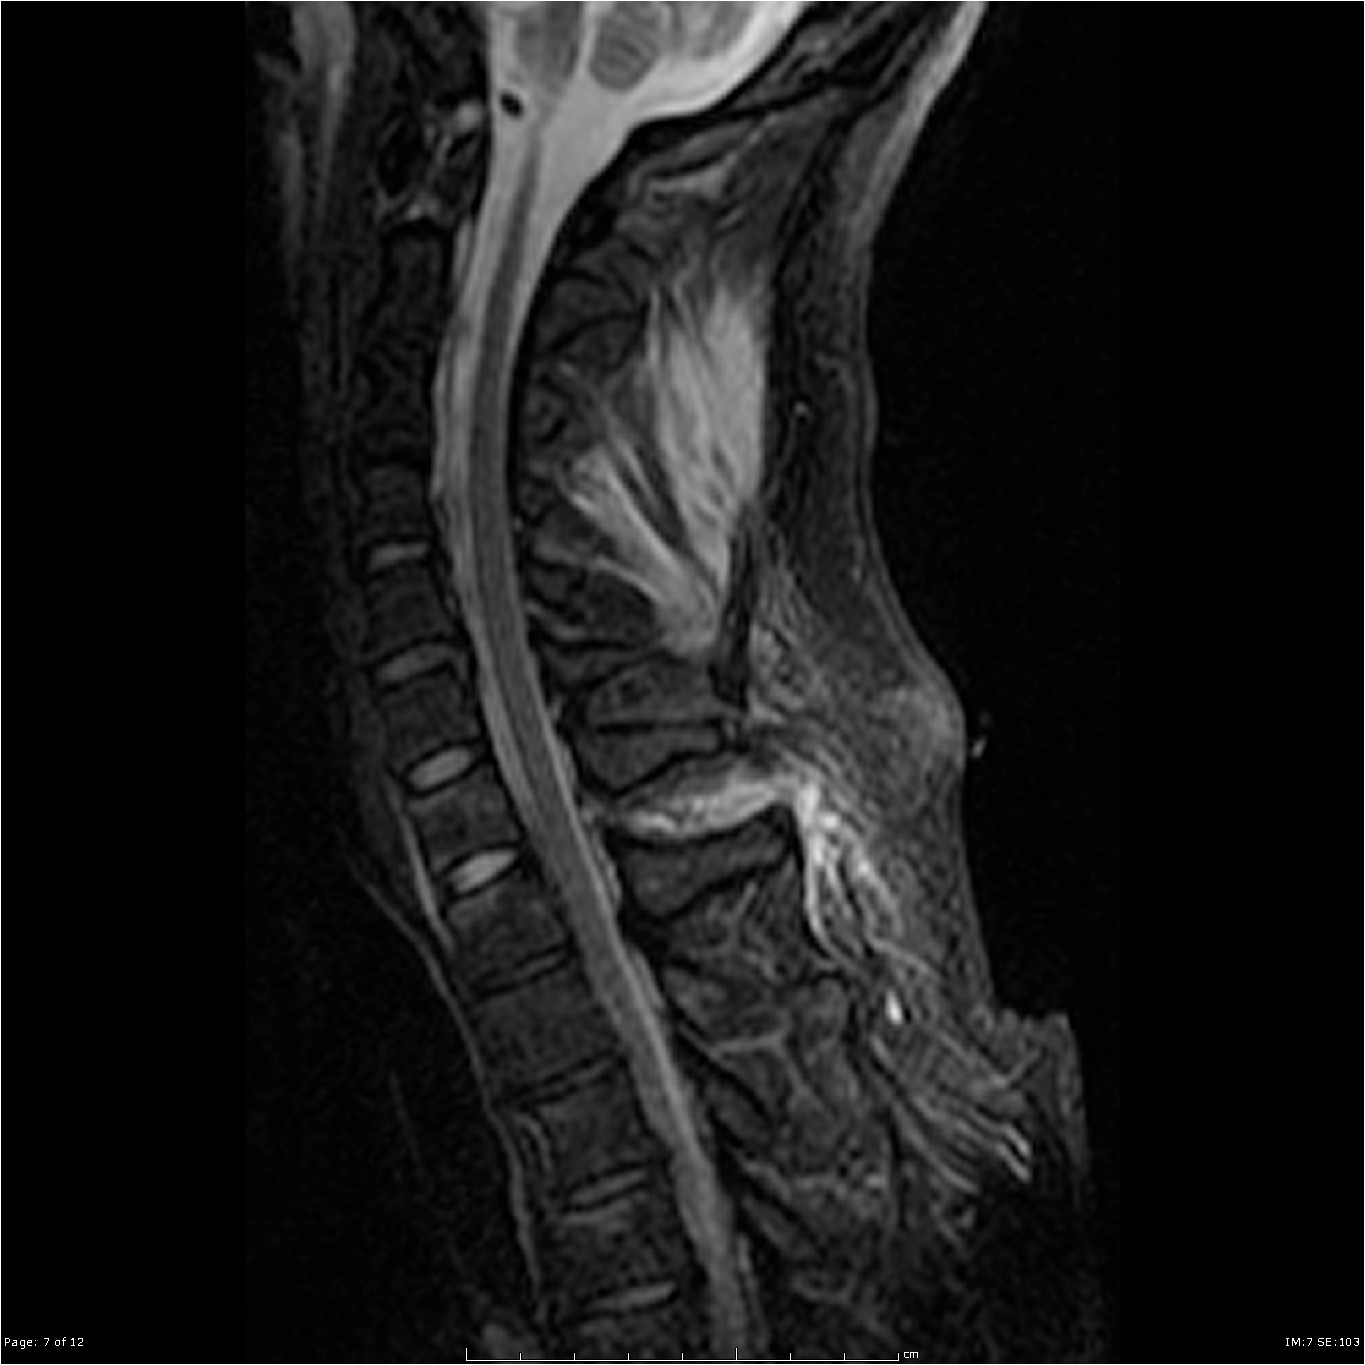

MRI of the neck showing Ligamentum flavum tear from C7-T1 not seen on CT

Soft tissue or ligamentous injuries (such as sprains or strains) may not be visible on CT and can cause prolonged pain. MRI can help assess these soft tissues, especially if symptoms do not improve with conservative management.